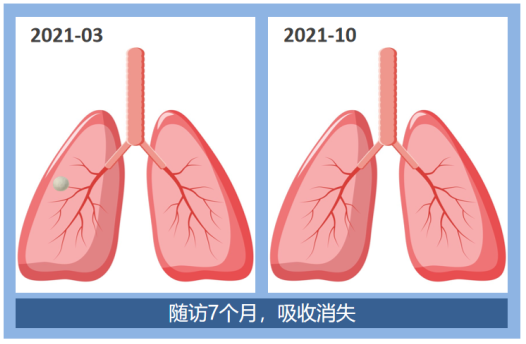

这是两例磨玻璃结节病例,肺结节既可以在三年的随访中保持不变,也可以在随访7个月后吸收消失了。